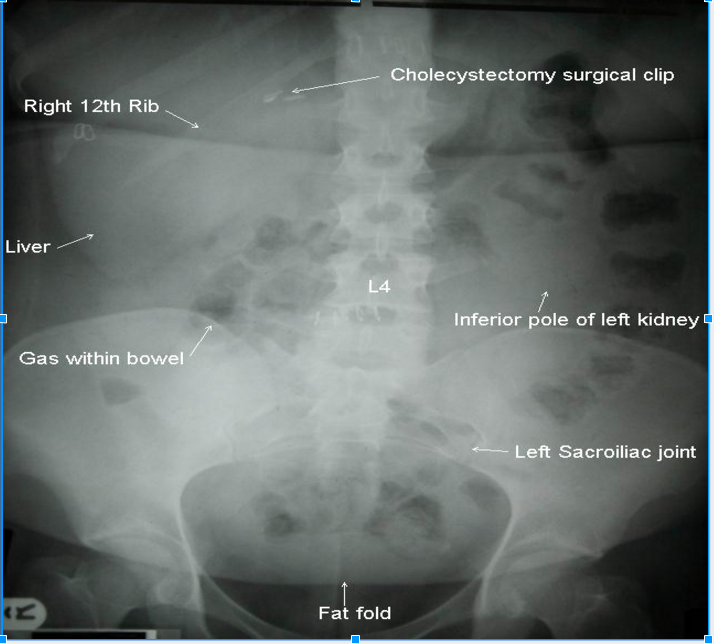

Normal Gas Pattern

See picture